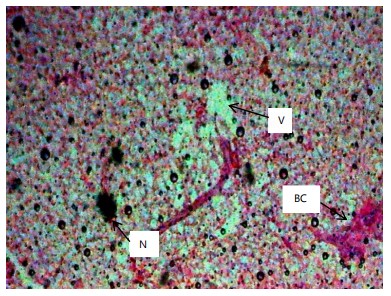

Histopathological examination of the liver and gill tissues of Clarias gariepinus juveniles revealed significant and concentration-dependent alterations following exposure to Bispyribac sodium herbicide, compared to the control groups, which displayed normal tissue architecture.

In the liver (Fig. 2-7), the control group (0.00 mg/L) exhibited normal hepatic structure with intact hepatocytes. Exposure to Bispyribac sodium induced a range of lesions, beginning at the lowest concentration of 0.59 mg/L with blood congestion, vacuolation, and necrosis. The severity and prevalence of these pathologies increased with concentration. At 1.97 mg/L, rupture of hepatocytes (RH) was observed, and the highest concentration of 2.95 mg/L resulted in the most severe damage, characterized by the addition of sinusoid dilation (DS) alongside the other noted lesions.